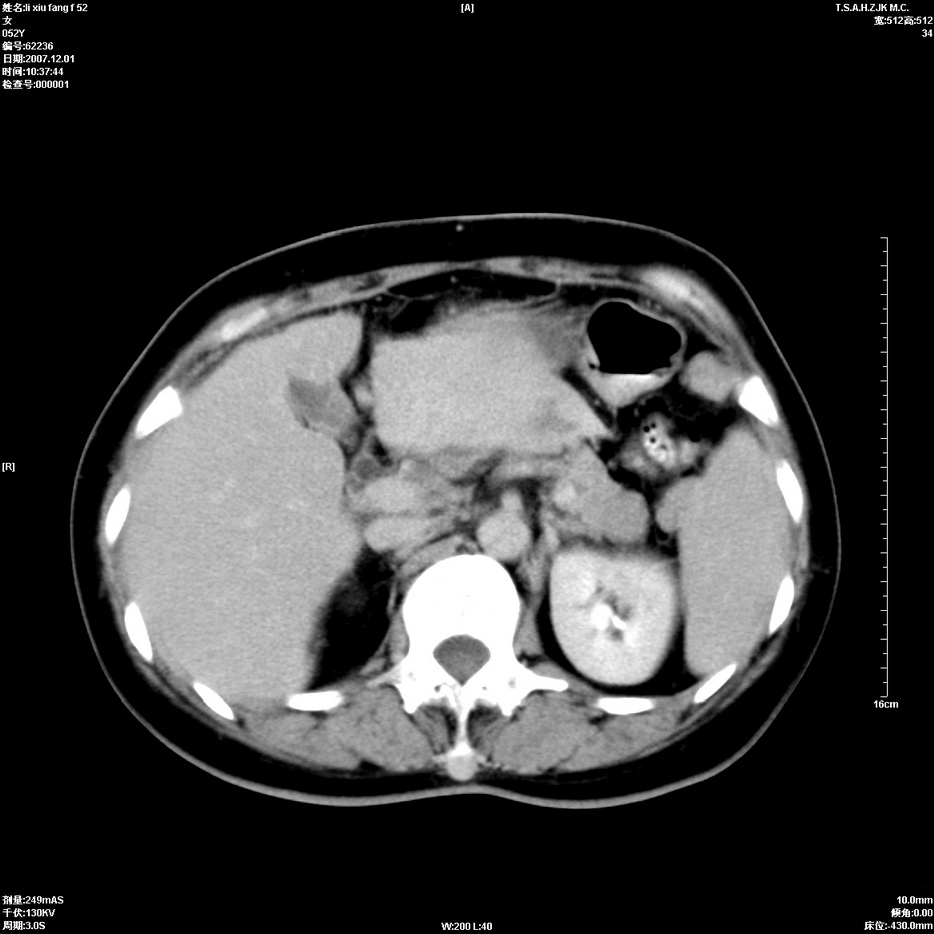

标题: CT12858:女,52岁,胎甲球蛋白861肝左叶占位,肝癌。下腔静 [打印本页]

标题: CT12858:女,52岁,胎甲球蛋白861肝左叶占位,肝癌。下腔静

肝左叶巨大低密度灶肿块,增强符合快进快出表现,有动静脉交通支;静脉期,下腔静脉内有充盈缺损,afp明显升高,支持肝癌并下腔静脉癌栓形成。

支持楼主   门静脉主干及左支癌栓形成

以下是引用拾荒者在2008-4-15 22:57:00的发言:[br]肝左叶巨大低密度灶肿块,增强符合快进快出表现,有动静脉交通支;静脉期,下腔静脉内有充盈缺损,afp明显升高,支持肝癌并下腔静脉癌栓形成。